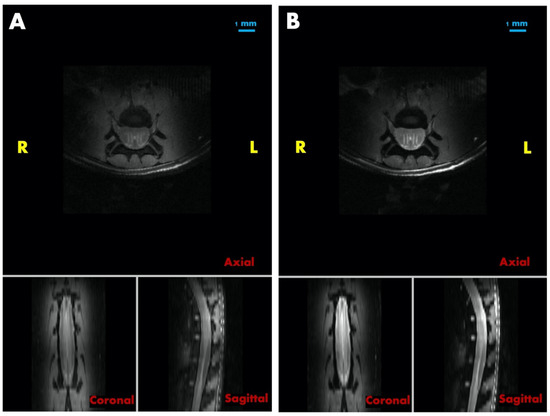

3.5. Post-Mortem MRI